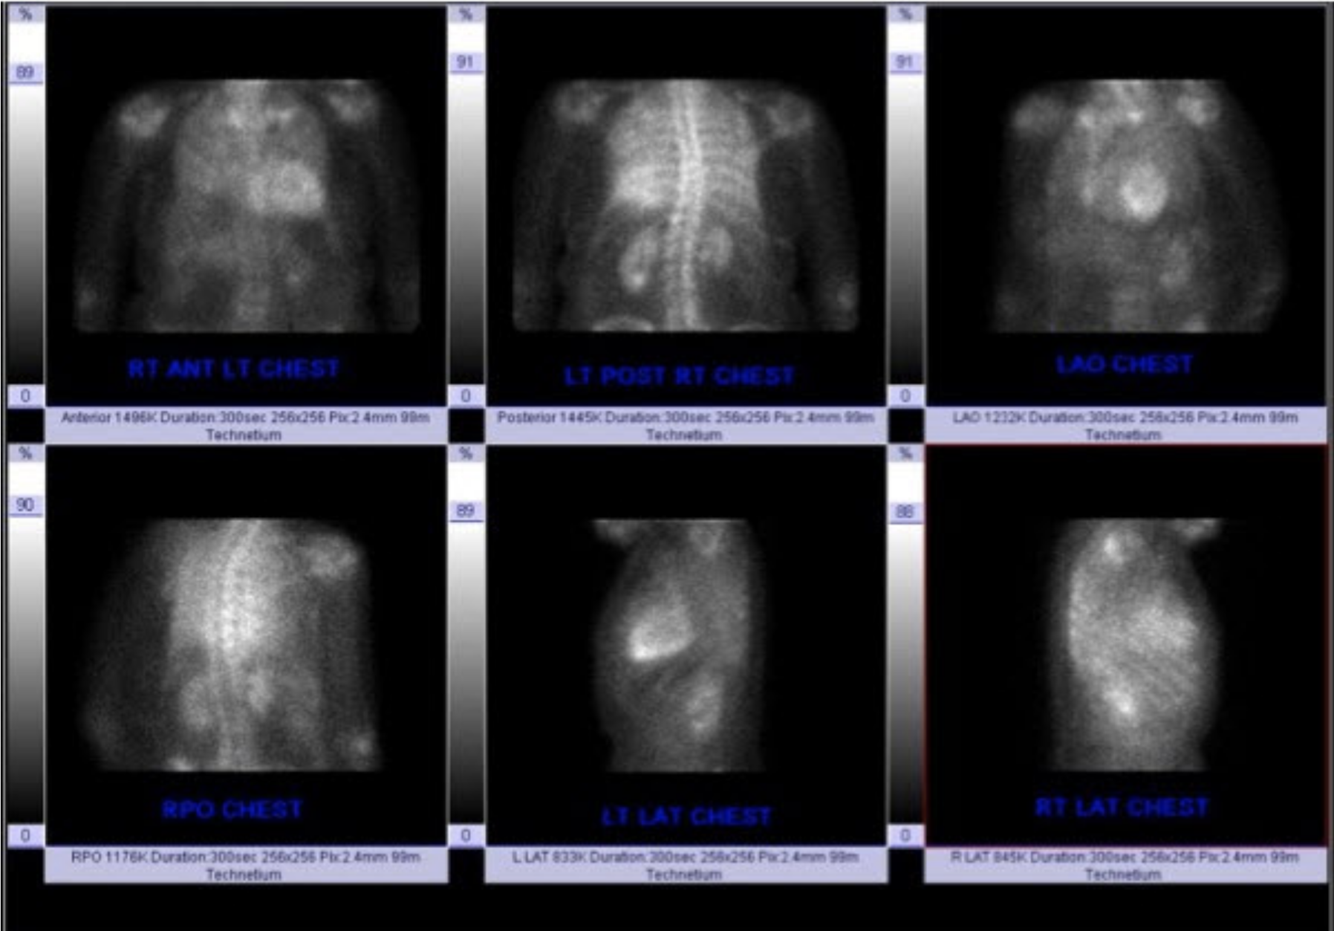

Describe the findings:

Scaling artifact